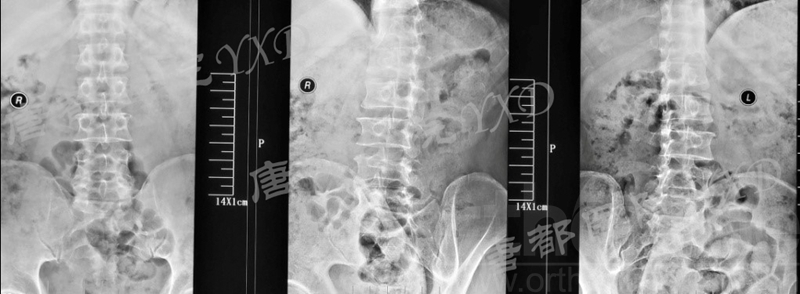

影像学检查:

诊断:腰椎椎间融合术后融合器后移

手术方案:显微镜辅助MI-TLIF腰椎翻修术

术中视频:http://api.orthonline.com.cn/attach/Case3.mp4(术中发现因前次手术全椎板及关节突切除,TLIF的第一步,即关节突关节的定位落脚点难以找到。显微镜下通过Kambin三角解剖位置,进行从外至内的解剖,寻找cage尾端;此外,因大量瘢痕渗血,难以进行充分止血;但在显微镜的照明和放大视野下,操作均可在不伤及神经的前提下进行。由于终板骨质吸收,椎间隙塌陷,导致术野内可同时看到出行根和走行根。而在显微镜下,能够通过调整景深和视线角度,精准充分处理椎间隙骨性终板。无手术并发症)

术后疗效:VAS左下肢1分、腰1分;左侧直腿抬高试验、加强试验阴性。